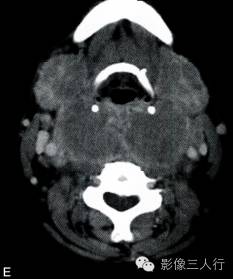

A~C.CT平扫横断面;D~F. CT增强横断面;G. HE×40

双侧甲状腺、颌下腺及咽淋巴环见多发结节融合状软组织影,边界不清,可见包膜,病灶密度欠均匀,内可见线样分隔,未见明显坏死及钙化,双颈各区可见大小不等的淋巴结,边界欠清,密度较均匀(图A~C)。增强横断面(图D~F)扫描双侧甲状腺、颌下腺及咽淋巴环病灶包膜及分隔可见明显强化,双颈淋巴结可见较明显强化。